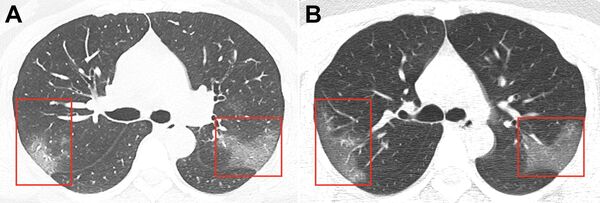

2020年2月3日, 01:42 (更新: 2022年2月15日, 20:18) 中國衛生部門公開一名感染2019-NSV冠狀病毒的女性患者的肺部圖片。

發表在《放射學》雜誌上的圖片是從一名在中國蘭州市住院的33歲女子的CT掃描圖片,她的體溫是39度。

第一張圖片顯示雙肺呈不透明的磨玻璃樣。 第二張圖片是三天後拍的,可以看到感染區正在擴大。